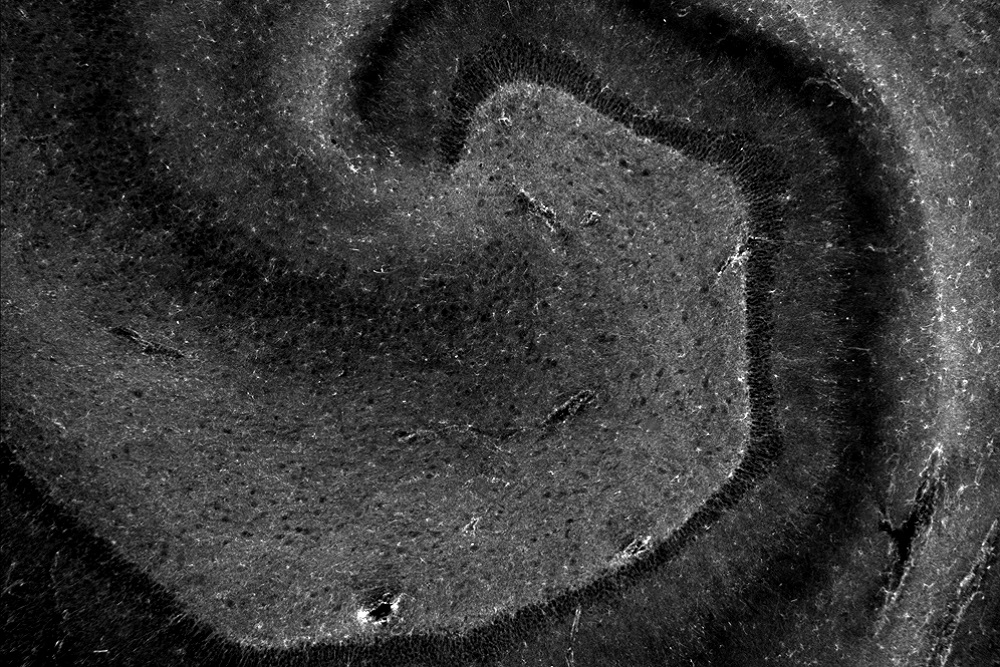

A Glance in the Brain

Submitted by: Natalia de Menezes Lyra e Silva, Post-Doctoral Fellow, Centre for Neuroscience Studies

Location of Photo: Centre for Neuroscience Studies, Queen’s University

Description of Photo: The primate brain is highly specialized, allowing us an incredible range of experiences. This microscopic photo captures cells within a brain region, the hippocampus, involved with learning and memory. Every lived experience that we are able to remember has boosted the formation of new connections in our brains. These connections are affected in diseases that impair memory, such as Alzheimer's disease (AD). Here, we can observe cells involved with the brain inflammatory response. These cells are upregulated in the brains of AD patients. This technique allows us to better understand how our brains work and how they are altered by diseases.